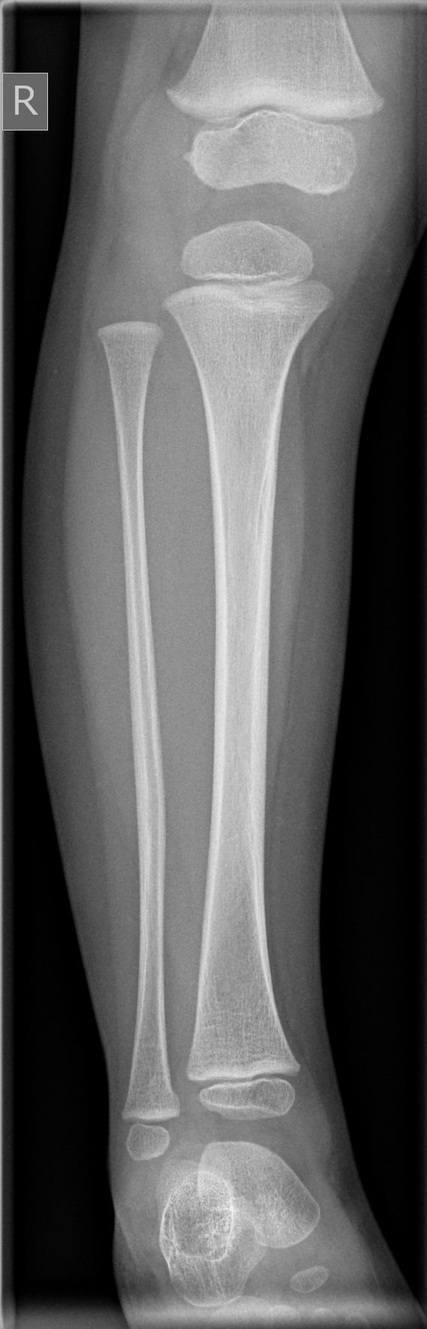

Unterschenkel a.p. und seitlich

Normalerweise ergeben sich bei Unterschenkelschaftfrakturen keine größeren diagnostischen Probleme. Aufnahmen in zwei Ebenen sind normalerweise ausreichend. In der Regel frakturieren Tibia und Fibula gemeinsam: „komplette Unterschenkelschaftfraktur“.

Zur sicheren Abschätzung von Rotationsfehlstellungen sollte immer der ganze Unterschenkel mit angrenzenden Gelenken abgebildet sein!

Isolierte Fibulafrakturen sind selten! Auch bei hohen Fibulafrakturen unbedingt nach primären Verletzungen des OSG fanden! Maisonneuve-Fraktur!

Bei Kindern auf Epiphysenfugenverletzungen achten Achsgerechte Stellung der Epiphyse in beiden Ebenen? Weite der Fugen (normalerweise 3-6mm)? evtl. Gegenseite zum Vergleich röntgen!